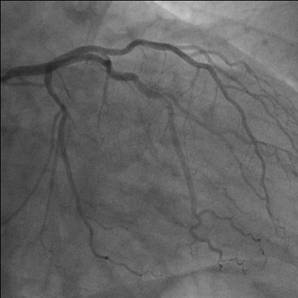

Ziel der Operation ist, jeder höhergradige Stenose an relevanten Coronarästen (Abb.1.) mittels Bypass zu überbrücken, es wird somit über arterielle oder venöse Bypässe in die zuvor minderversorgten Areale wieder ausreichend Blut transportiert (Abb. 2.). Triviale Äste können jedoch wegen ihres kleinen Durchmessers nicht versorgt werden. Der aortocoronare Mehrfachbypass unter Verwendung der Arteria thoracica interna (linke innere Brustarterie) ist heute absoluter Standard an jeder herzchirurgischen Klinik und die häufigste Herzoperation weltweit (Abb.3.).

Abb. 1. Darstellung der Herzkranzgefäße mittels Coronarangiographie (rechte und linke Kranzarterie) zur Beurteilung von Engstellen (Stenosen) vor einer allfälligen Intervention.